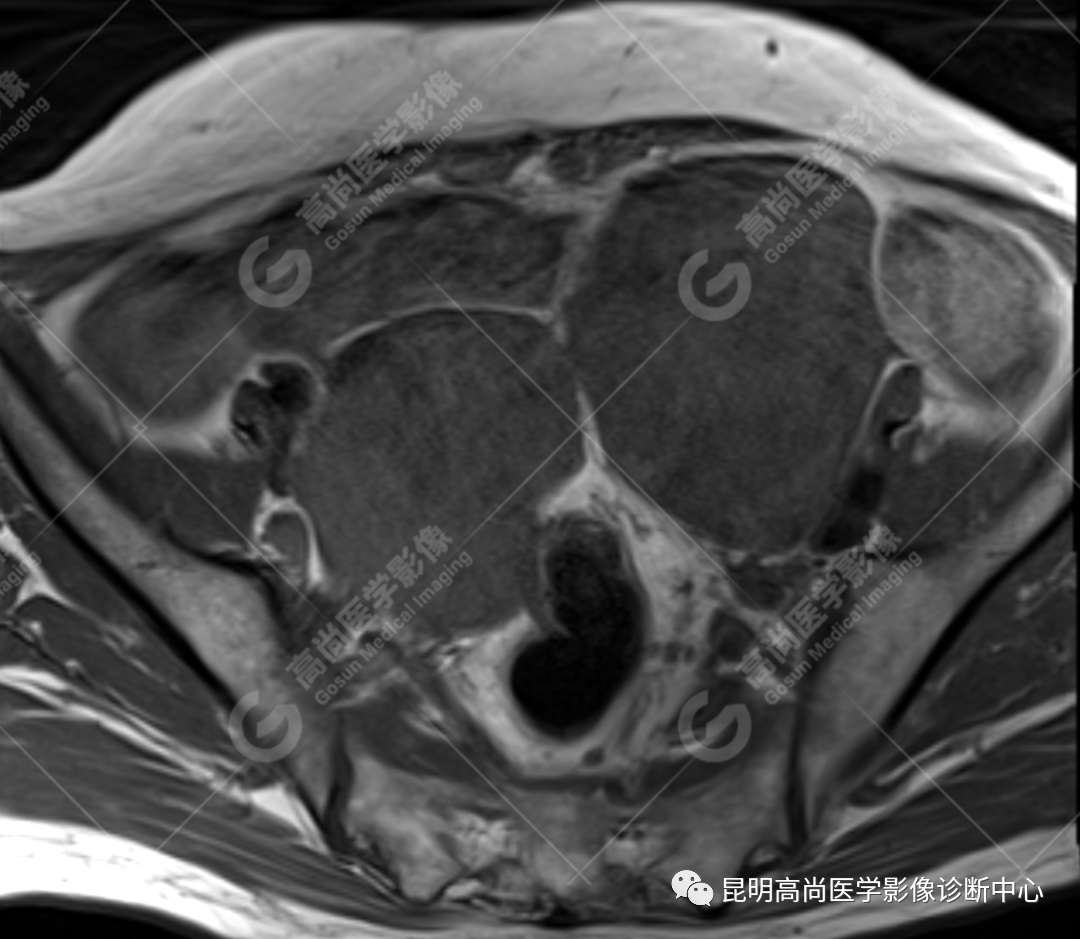

检查图像

影像诊断

子宫、附件未见显示;下腹部及盆腔内巨大占位,考虑恶性肿瘤,肉瘤可能,阴道及肛管受侵,建议活检。

MRI 表现

不规则菜花状或息肉状肿物,子宫内膜正常 T2WI 清晰连续的高信号消失,取而代之是中高、高信号,不均匀混杂信号,信号强度低于内膜正常信号强度,T1WI 上内膜信号增高,子宫肌层明显变薄,未受侵者肌层信号均匀,因肿物组织来源不同,病变信号复杂,以 T2WI 表现为等高混杂信号为主。因病灶较大,可合并囊变坏死及肿瘤出血。